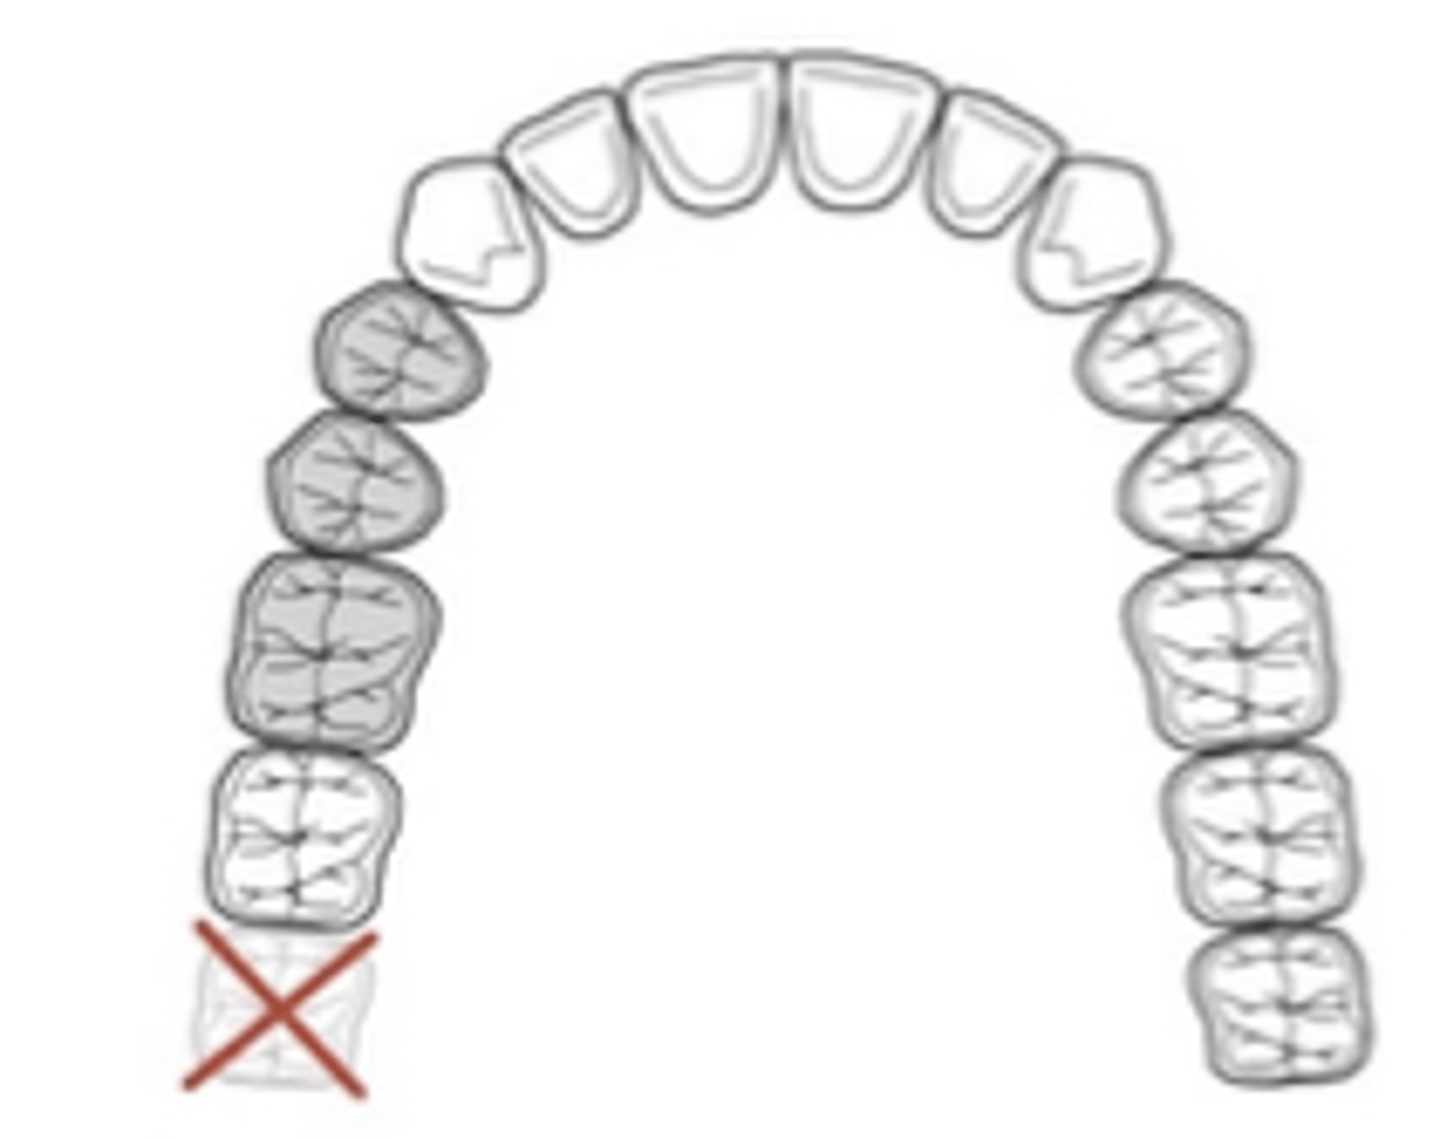

Kennedy Class I

Tooth and tissue supported:

bilateral edentulous area posterior to natural teeth

which Kennedy Class?